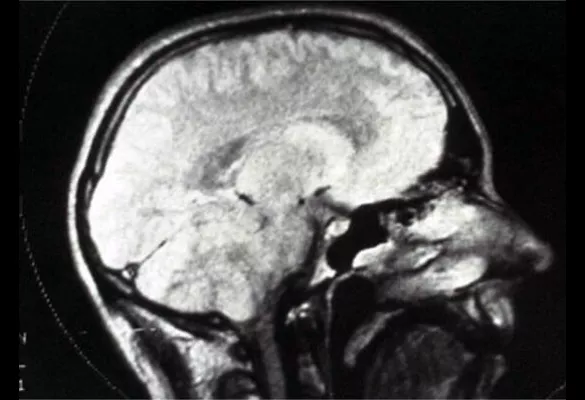

Soft tissue imaging

1983

Radiology made the leap from imaging bones and hard structures to visualizing soft tissue with the introduction of the MRI. Much early research and development for this tool was conducted at UCSF.